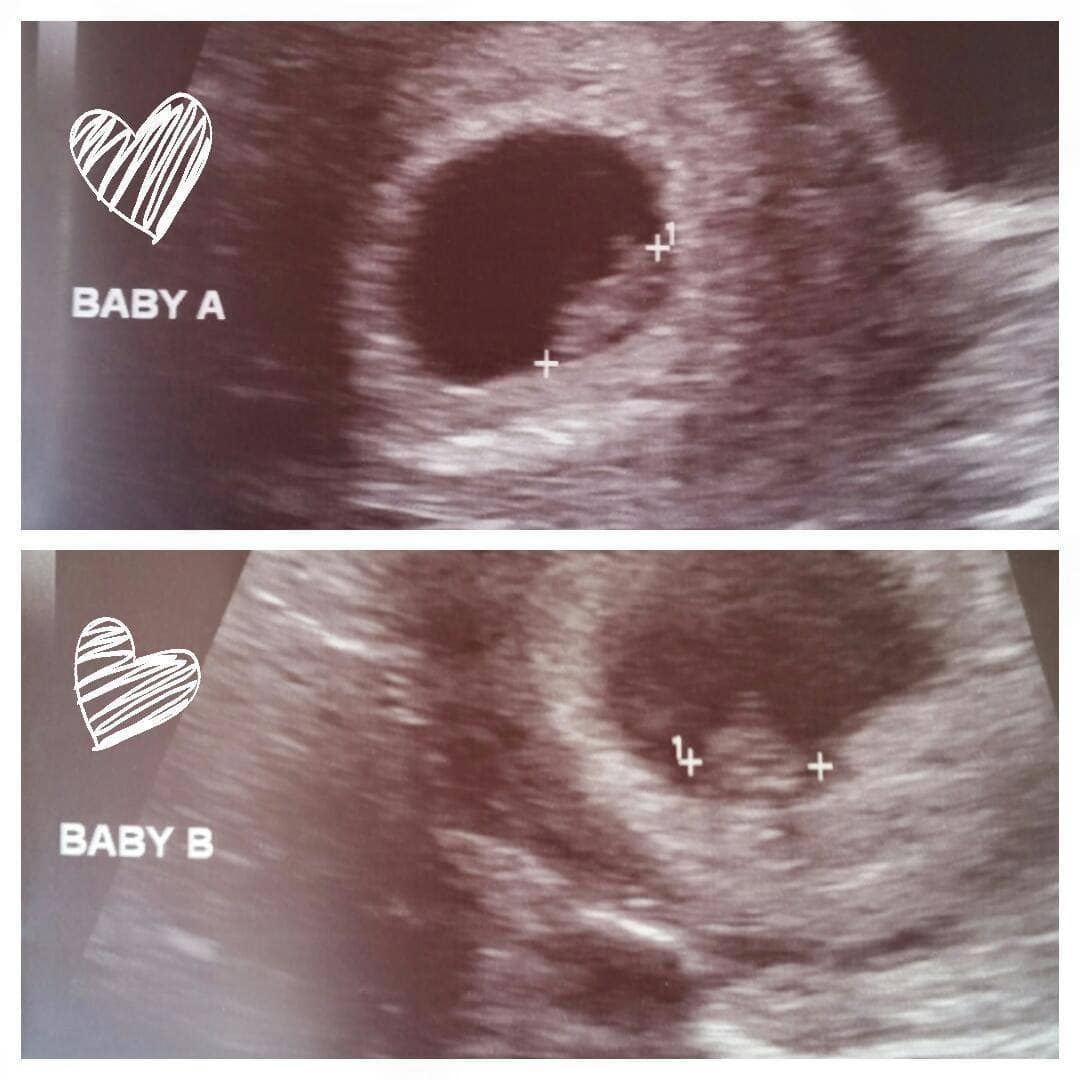

REMINDER: Don’t forget to take a belly shot! 8 week sonogram

Ultrasound Photos – 8 Week Sonogram

8 week sonogra